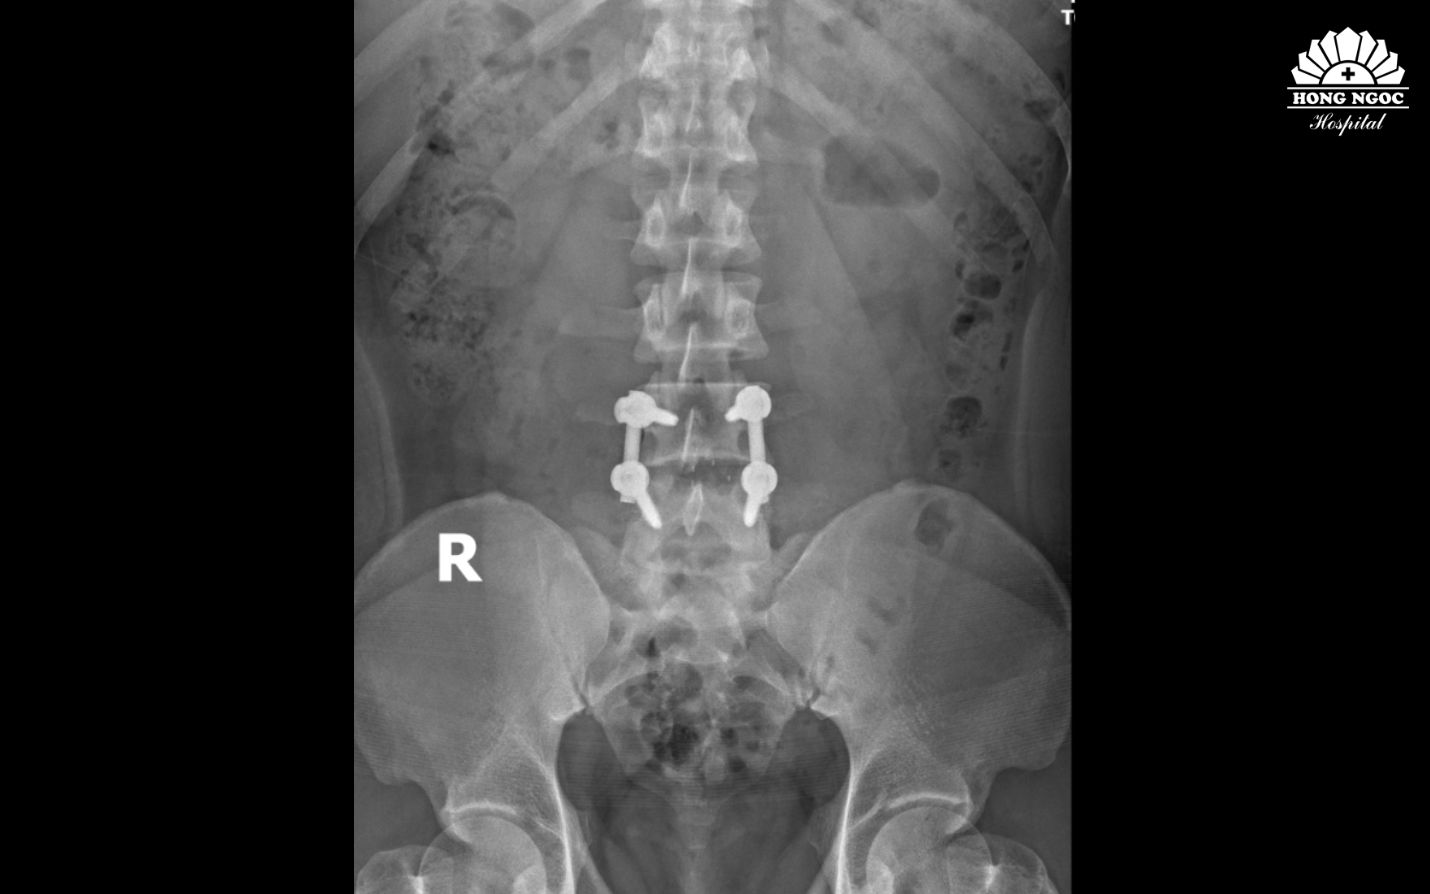

Qua thăm khám và kết quả chụp cộng hưởng từ (MRI), bệnh nhân được chẩn đoán thoát vị đĩa đệm cột sống thắt lưng L4/L5 gây chèn ép rễ thần kinh, cần phẫu thuật để tránh biến chứng liệt.

Hình ảnh thoát vị đĩa đệm cột sống L4/L5 qua phim chụp

Phim chụp sau phẫu thuật thoát vị đĩa đệm, hàn xương và nẹp vít đốt sống L4/L5